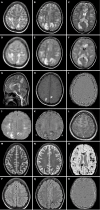

Background: Acute hemorrhagic leukoencephalitis (AHLE), also known as Weston-Hurst syndrome, is a very rare and fulminant form of demyelinating disorder. It is considered a hyperacute and severe variant of acute disseminated encephalomyelitis. Clinically, patients present with fever, headache, seizures, and altered sensorium, which can rapidly progress to coma or death. Magnetic resonance imaging (MRI) is the investigation of choice and plays a pivotal role in diagnosing AHLE. The purpose of this article is to make readers familiar with the typical MRI features of AHLE and to discuss differentials.

Case summary: This case series reports the clinical presentation and typical neuroimaging findings in four patients diagnosed with AHLE. All patients presented with acute neurological symptoms, such as severe headaches, seizures, and altered consciousness, often following a history of fever suggesting an infectious etiology. Additionally, laboratory investigations demonstrated elevated levels of serum inflammatory markers and neutrophilic pleocytosis on cerebrospinal fluid analysis, supporting a post-infectious etiology. MRI findings consistently revealed characteristic white matter lesions with hemorrhagic foci and vasogenic edema, indicative of widespread demyelination characteristic of AHLE. The outcomes varied, with two patients surviving but experiencing neurological sequelae, while two others unfortunately succumbed to the disease. The clinical data, laboratory results, and imaging findings from this case series were systematically compared with those from previously published studies. The key similarities and differences in clinical presentation, imaging characteristics, and outcomes are presented in a tabulated format.